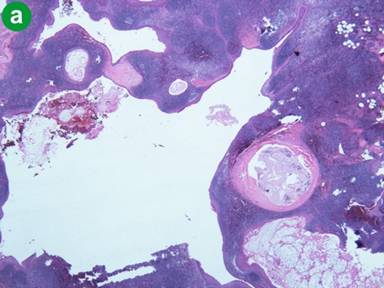

The patient is a 62-year-old male who presented to a rural clinic with complains of vague left-sided abdominal pain. A Computed tomography (CT) scan was obtained which showed a left-sided retroperitoneal mass with a possible cystic component (Figure 1). Resection of the mass was advised and the patient was transferred to our tertiary academic medical center. Abdominal surgical exploration revealed a large mass containing a cystic cavity (4.8x3.7x1.9 cm in aggregate) consisting of hemorrhagic fatty soft tissue and purulent appearing debris originating from the tail of the pancreas. The cyst was removed and sent for pathologic examination. Microscopy revealed multiple epidermoid cysts within accessory splenic tissue (Figure 2). The cysts were lined by stratified squamous epithelium, some of which was keratinizing, and were variable in size. Several cysts appeared to have ruptured and had surrounding fat necrosis and foreign body giant cells. The lining of the cysts was positive for CEA on immunohistochemistry. The findings are consistent with a benign epidermoid cyst arising within accessory splenic tissue in the tail of the pancreas. The patient recovered without complication.

Figure 2. a. Microscopic image of multiple cysts with stratified squamous epithelium within splenic parenchyma. b. Immunoperoxidase positivity for CEA in the epithelium of the cyst. |